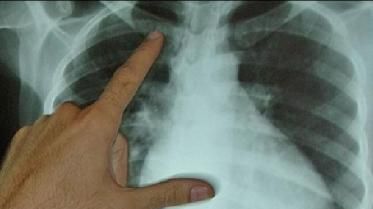

Pericol de epidemie TBC într-un oraş din România

Pericol de epidemie TBC în trei şcoli din Drobeta-Turnu Severin, unde mai mulţi elevi şi profesori s-au înregistrat cazuri.

Cea mai gravă situaţie se înregistrează la Colegiul Tehnic „Lorin Sălăgean”, unde doi elevi au fost descoperiţi pozitiv, iar ulterior, alţi şase au devenit suspecţi că ar fi contactat bacilul. Şi la o şcoală gimnazială au fost înregistrate trei cazuri. Unul este la un profesor, dar nu este vorba de TBC pulmonar, deci cazul nu este contagios. Celelalte două sunt la un elev de clasa a VIII-a şi la un alt profesor care a mai fost infectat şi la care boala a recidivat. Cel de-al treilea caz se înregistrează la Liceul Halânga, informează Radio Craiova.